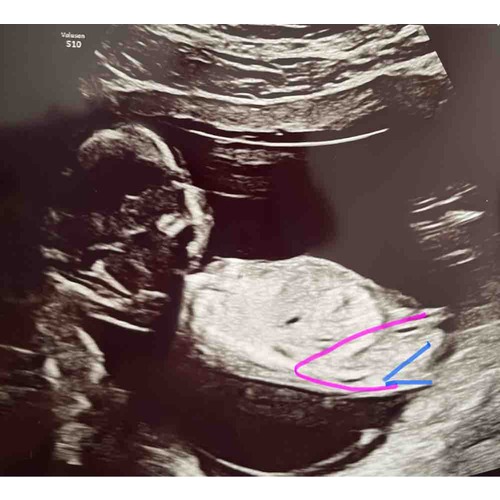

Foto 2: ook 13+1 week. Zelf denk ik het niet te kunnen zien

Ik waag toch een gokje: Meisje

Ik denk een jongentje